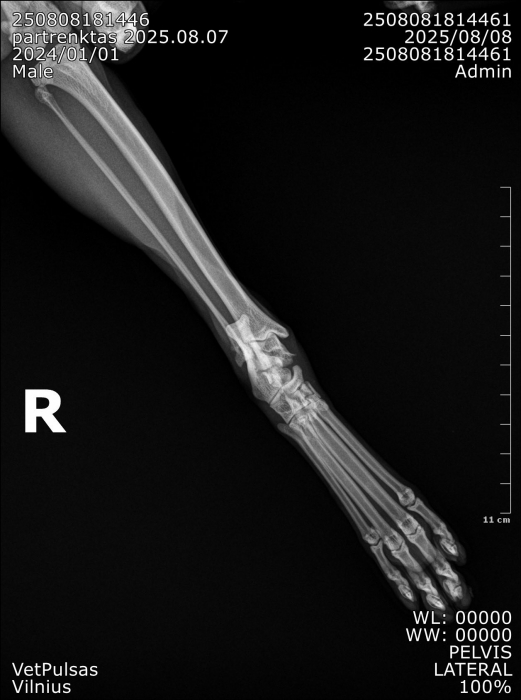

Į veterinarijos kliniką žmonės atvežė automobilio nutrenktą katinuką. Atlikus rentgeną paaiškėjo, kad abi užpakalinės kojos per sąnarius suknežintos į skeveldras. Vienos kojos raiščiai nutraukti. Apžiūrėjusi nuotraukas ir įvertinusi skeveldrinius lūžius chirurgė informavo kad operacija bus itin sudėtinga ir brangi. Vienu metu ji galėtų atlikti tik vienos kojytės operaciją, o po savaitės ar daugiau žiūrint kokia gyvūno būklė galės operuoti antrą. Visa tą laiką katinukas bus klinikos stacionare.

Chirurgė perspėjo kad operacija, gydymas ir pooperacine slauga klinikoje kainuos tikrai pakankamai daug nes užtruks mėnesį ar net daugiau laiko.